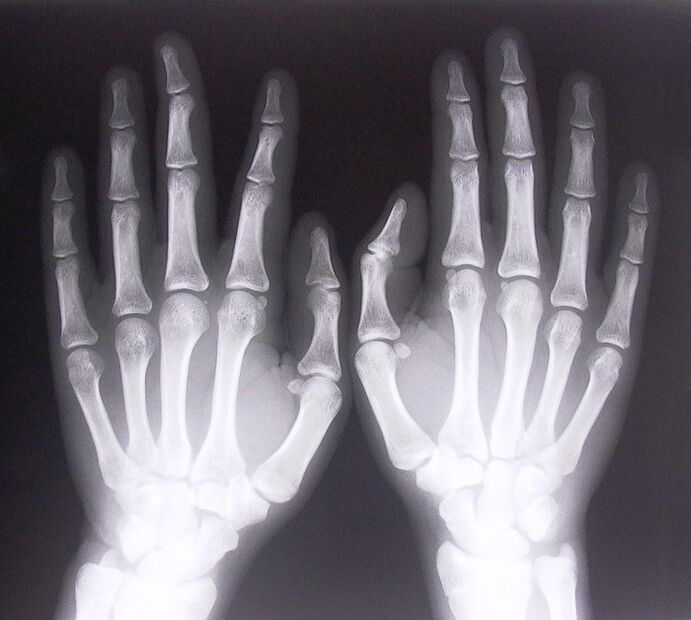

1. Take x-rays.

X-ray as a way of diagnosing pain in finger joints